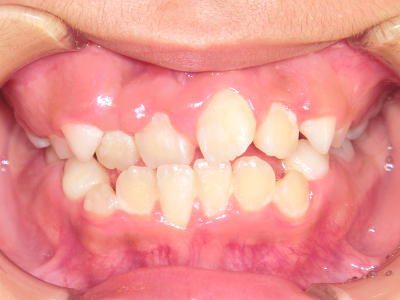

歯並びの相談に来られるお子様は、口呼吸をしているケースが多く、これが歯並びに大きな影響を与えています。

↓ - さまざまな不正咬合が生じる

ないき歯科クリニックでは、上あごの成長不足を補い、鼻呼吸を獲得しつつ歯列を整え、将来のお口をより健康な状態にすることをゴールに定める矯正治療をおこなっています。